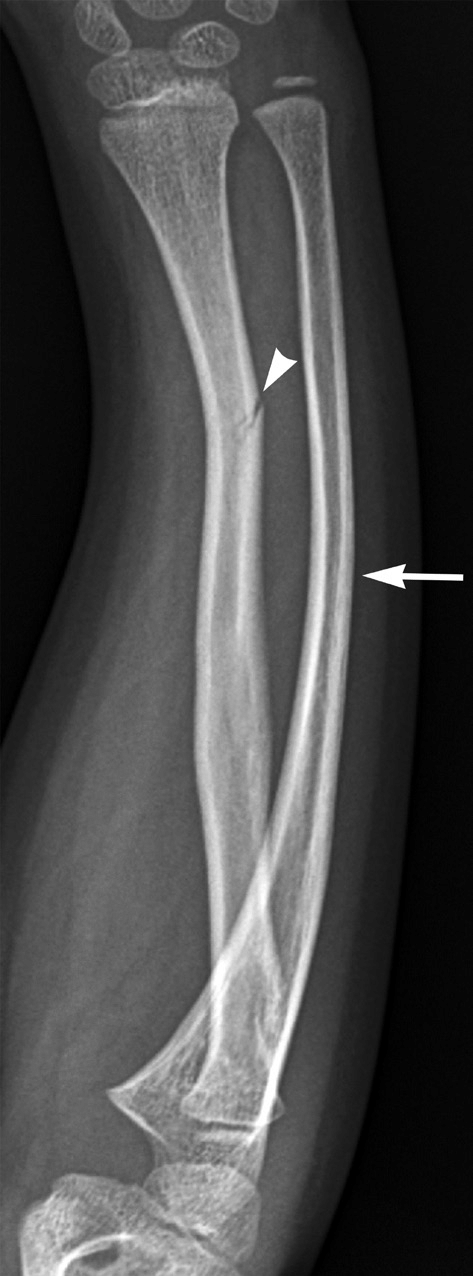

What is going on in this radiograph?

Greenstick fracture of the radius with associated plastic deformation (but not fracture!) of the ulna.